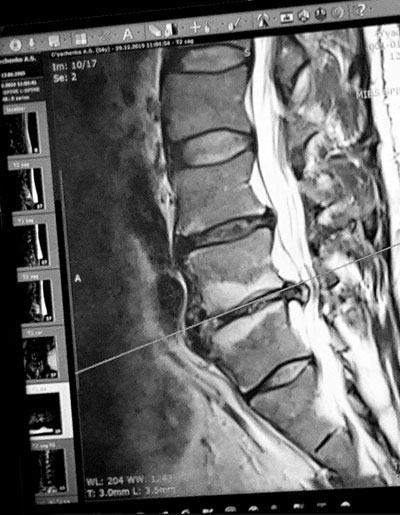

Сделал МРТ - обнаружили межпозвоночную грыжу.

- Она у меня выдающаяся аж на 12 мм, - сообщил Александр. - Благодаря лечащему доктору я по-прежнему на боевом посту и вполне в состоянии изображать здорового героя. Но мы только в самом начале пути к исцелению. От первой помощи полегчало, но о радикальных изменениях говорить пока рано.